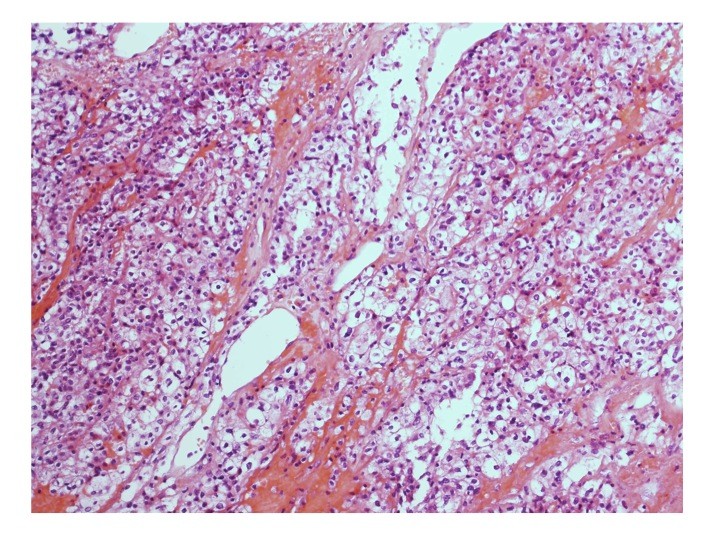

- Peut-on croire en l’histologie ?

Nathalie RIOUX LECLERCQ (Rennes)